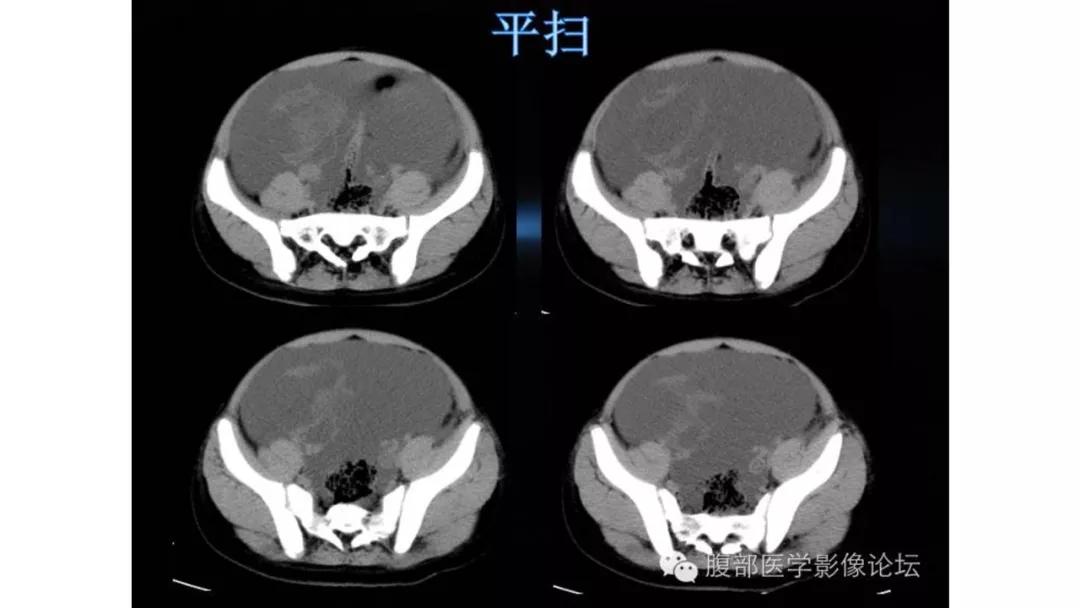

上皮性肿瘤:最常见,恶性多(卵巢癌),良性少。好发于50Y以上,发现时多为中晚期。多呈囊性或以囊性为主的囊实性肿块,完全实性者少见。形态多数不规则,边界模糊,囊壁及房间隔常不规则增厚,菜花样肿物或壁结节,囊实性区域分界不清,实性肿瘤常有不规则低密度或坏死区,可有边界模糊沙粒状或块状钙化,中-高度强化。良性者边界清晰,囊壁薄光整,无壁结节,实性部分呈无或轻度强化。

恶性者常呈实性或混杂性肿块,多数边界清楚,可伴有不规则沙粒状钙化。无性细胞瘤常为实性肿块,轻度强化,内胚窦瘤实性成分明显强化,不成熟畸胎瘤呈混杂密度。结合年龄及临床生化检查,有助于诊断。